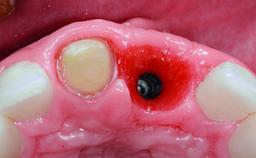

Replacement of a Compromised Upper Right Central Incisor: Hard- and Soft-tissue Augmentation, Late Placement of an RC Bone Level Implant

# of Implants 1

Type of Implants Two-Piece

Placement Protocol Early or late implant placement